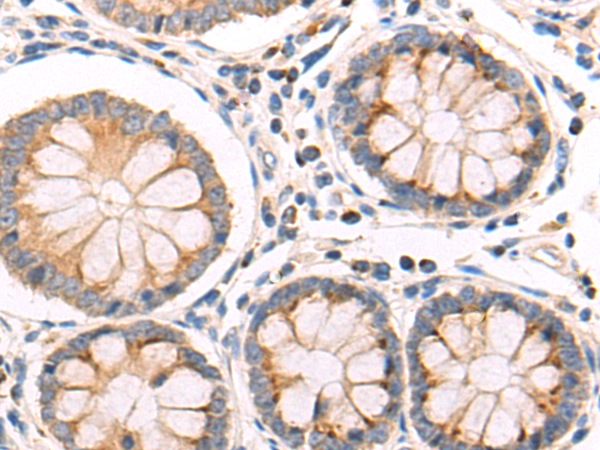

分类: 科研抗体货号: P09445别名: HSPC065应用: IHC反应种属: Human, Mouse